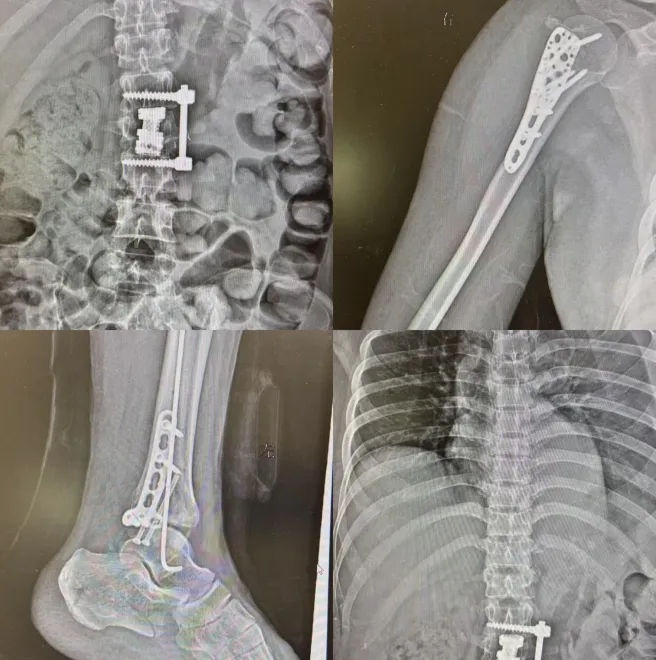

2025年 1 月 26 日,对 36 岁的吴女士(化名)来说,是生命中最灰暗的一天。产后抑郁的她从 9 楼坠落的瞬间,臀部和腿部先着地,巨大的冲击力让身体像被拆散的积木 —— 右侧肩膀、右小腿、双脚、骨盆、肋骨、胸椎、腰椎、骶骨…… 全身多处骨折,伴随着大量出血,意识也渐渐模糊。

术后,病情依然危重的她被转入 ICU。接下来的十几天里,她又经历了三次手术,身体像被反复拆开又缝合的布偶,疼痛成了清醒时唯一的感知。

2 月 13 日,为了进一步康复,吴女士转至我院。那时的她,全身被固定支具和纱布缠绕,稍微一动就疼得冒冷汗,肢体活动完全受限,吃饭、穿衣、翻身这些最基本的事,都需要别人帮忙。更让人揪心的是,她总是沉默地躺着,眼神空洞,仿佛对周遭一切都失去了兴趣。